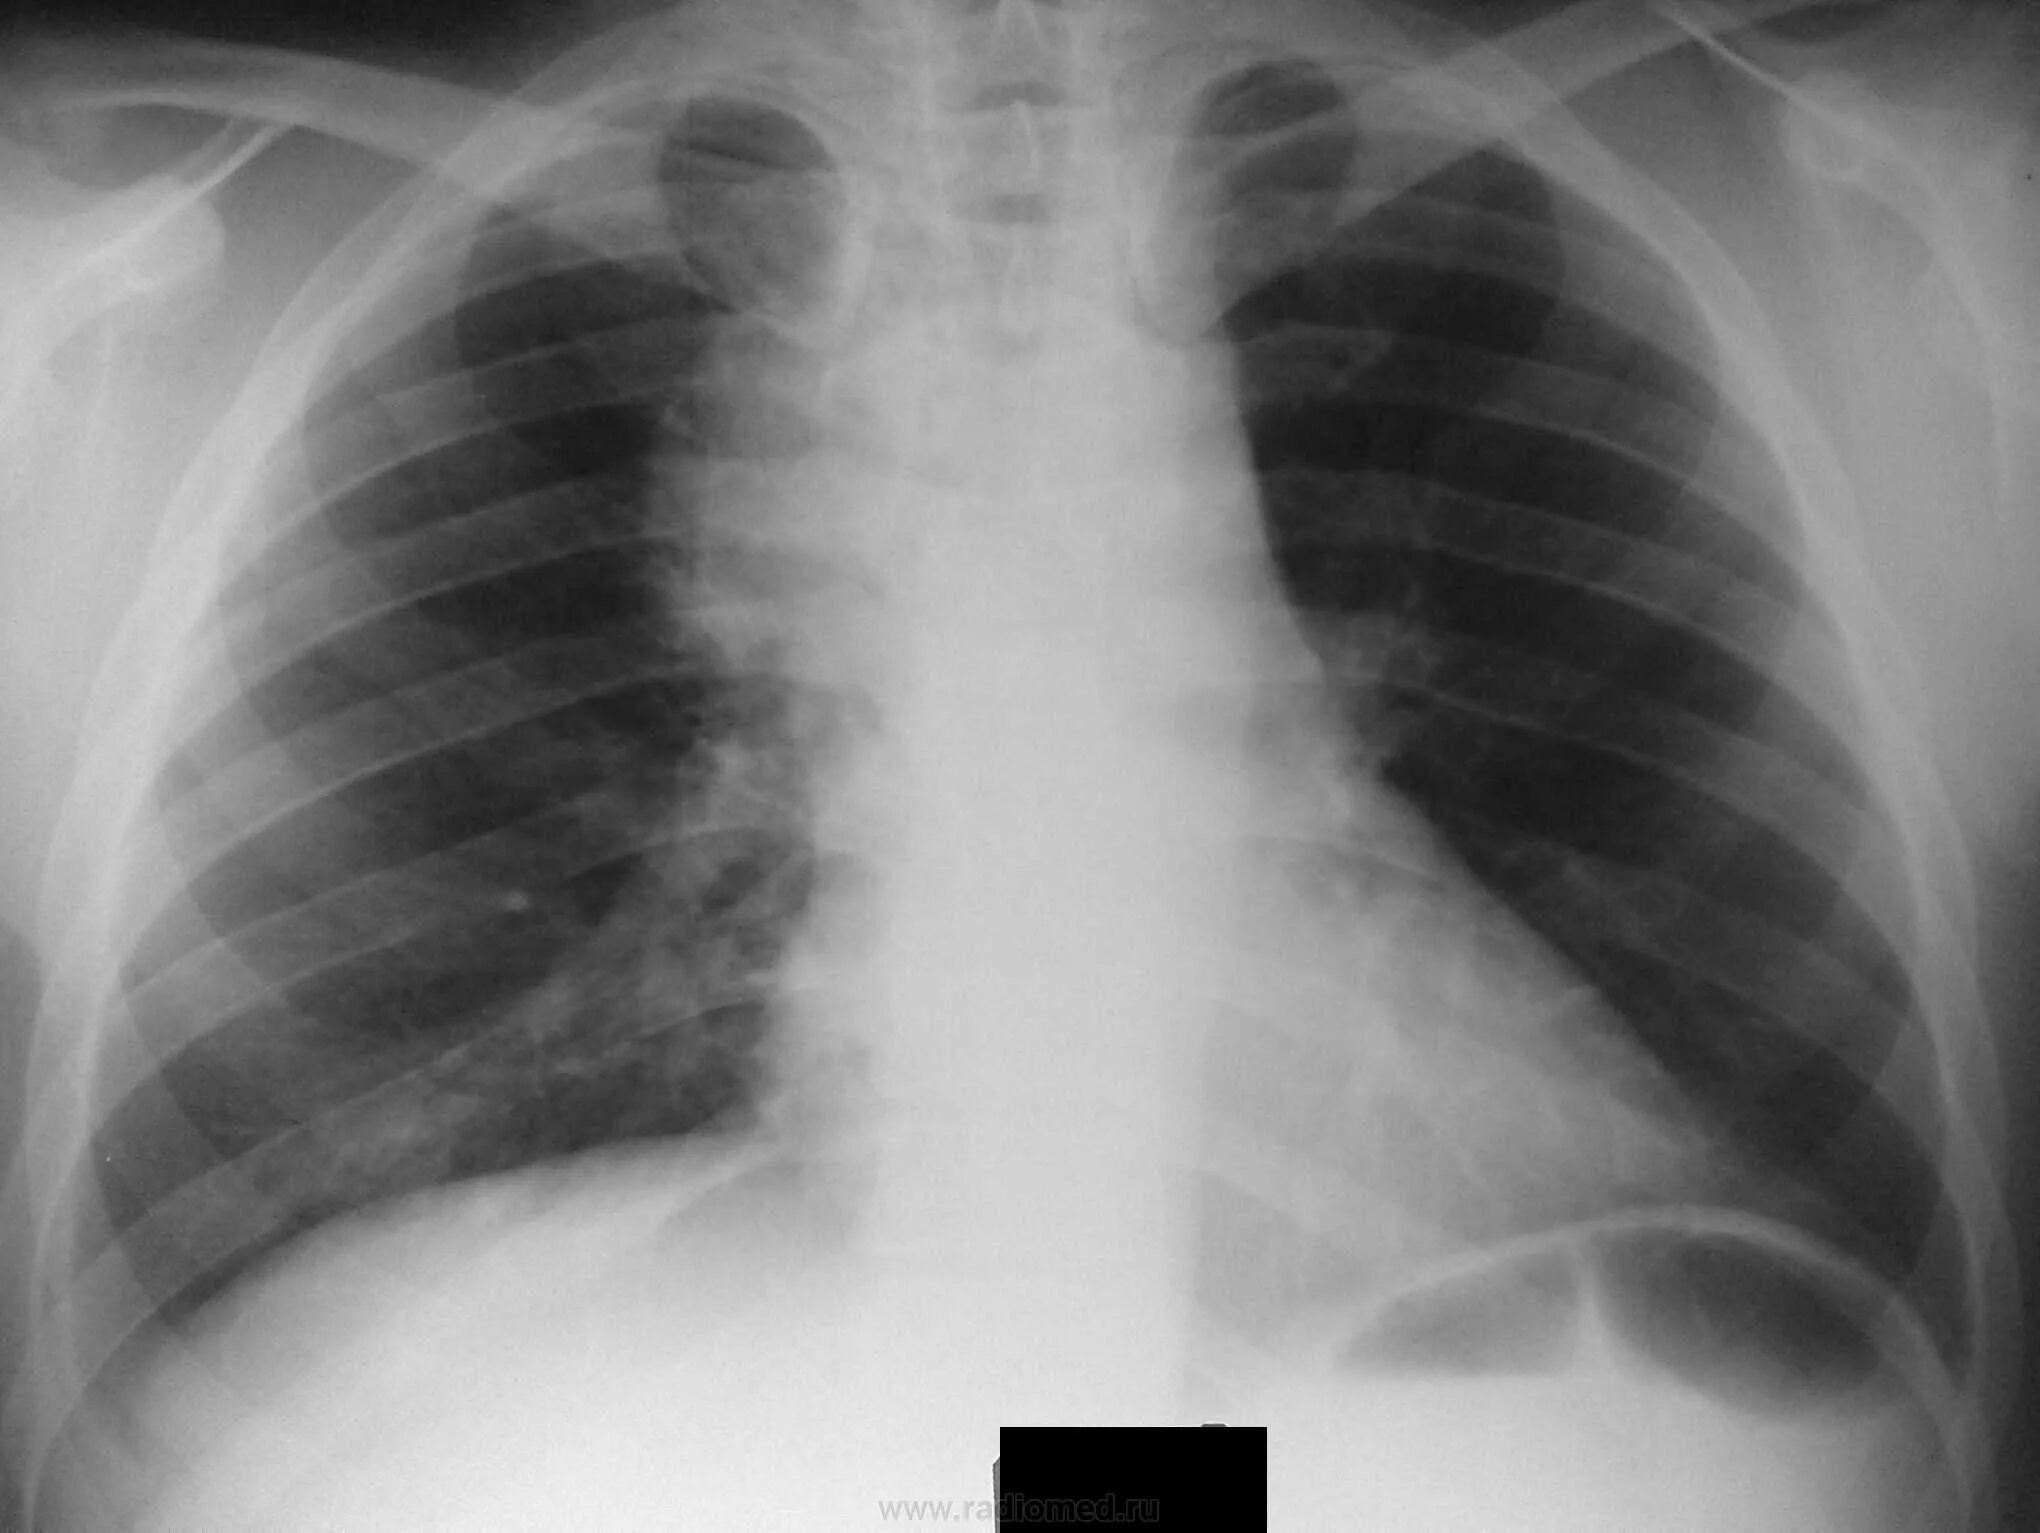

Медиастинит причины